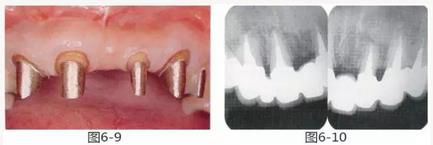

圖6-9 牙周外科治療5個月后,最終取模前的狀態(tài)?;乐車@得了充足的附著齦。

圖6-10 佩戴最終修復(fù)體時的X光照片。